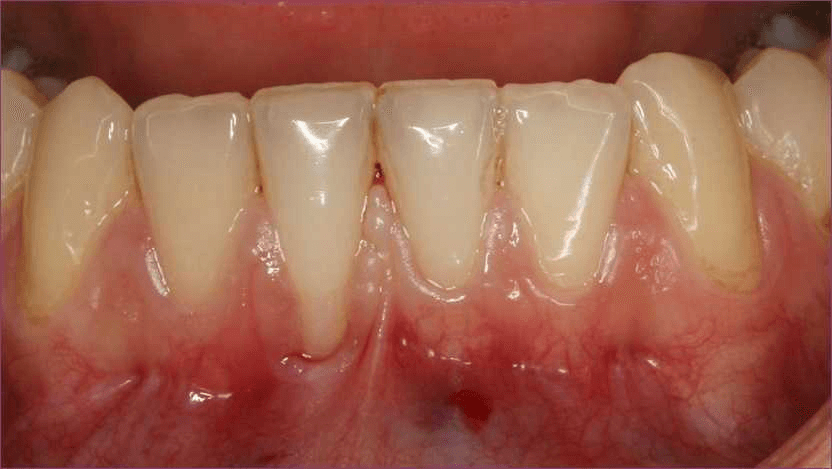

Kezdjük az alapokkal. A fogíny egy rugalmas, ellenálló hámmal borított kötőszövet, amely az állkapocs csontjait, illetve a fognyakat borítja. Egészséges állapotban halvány rózsaszín, és az egész fognyakat takarja. Az ínyrecesszió, más néven ínyvisszahúzódás azt jelenti, hogy a fogíny visszahúzódik a fognyakról.

- Nagyobbnak, hosszabbnak tűnnek a fogak. Ez egy optikai csalódás, amit az okoz, hogy a fognyak is kilátszik

- Fognyaki érzékenység. A szabadon maradt fognyak érzékeny a hidegre, melegre, illetve az édes vagy savanyú ételekre

A legnagyobb probléma az, hogy az ínyvisszahúzódás gyakran nem fájdalmas. Azaz sok idő eltelhet, mire észleljük a problémát, és akkor lehet, hogy a folyamat már nem visszafordítható. Időben történő felismerésekor viszont, az esetek többségében a folyamat megállítható és helyreállítható.

Az egyedüli valódi kezelés az ínyplasztika. Az ínyplasztika egy olyan beavatkozás, amely során visszaműtjük az ínyt a fognyakra. Bár az eredeti állapotot visszaállítani nem mindig lehetséges, komoly javulást tudunk elérni.